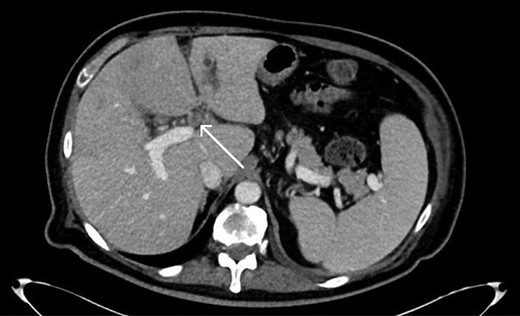

Abdominal imaging findings: axial computed tomography (CT) scan showing the intrahepatic dilation of the left sided biliary system (arrow) from cranial (A) to caudal (B), diffusely thickened gallbladder wall (C, arrow) and left intrahepatic abscess (D, arrow).

Repeat CT imaging revealed continued thrombosis of the left portal vein and anterior branches of the right portal vein and right hepatic artery (Fig. 3). Due to persistent left intrahepatic abscess and concern for an underlying obstructive process in the left biliary system, the patient underwent an endoscopic retrograde cholangiopancreatography (ERCP) which revealed choledocholithiasis which was removed followed by sphincterotomy and stent placement. He subsequently underwent a spyglass™ procedure which noted a left biliary tract occlusion secondary to a mass which was biopsied. Pathology, however, was noted to be benign with debris and bile crystalline material and rare fragments of fibrous tissue with biliary-type epithelium.

Axial CT scan showing thrombosis of the left portal vein (arrow).